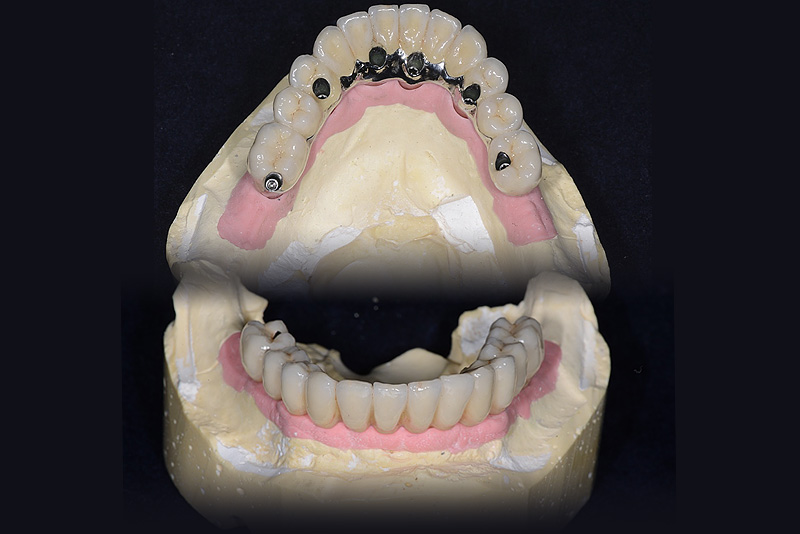

Vengono utilizzati 2 tipi di provvisori: il primo, cementato ai denti vicini, viene utilizzato dal momento dell’estrazione del dente fino ad impianto osteointegrato (circa 6 mesi); il secondo, avvitato direttamente all’impianto, ha una funzione di prova estetica ma soprattutto di guida per la maturazione dei tessuti gengivali peri-implantari portandoli verso la maturazione completa prima di posizionare la corona finale in disilicato di litio.